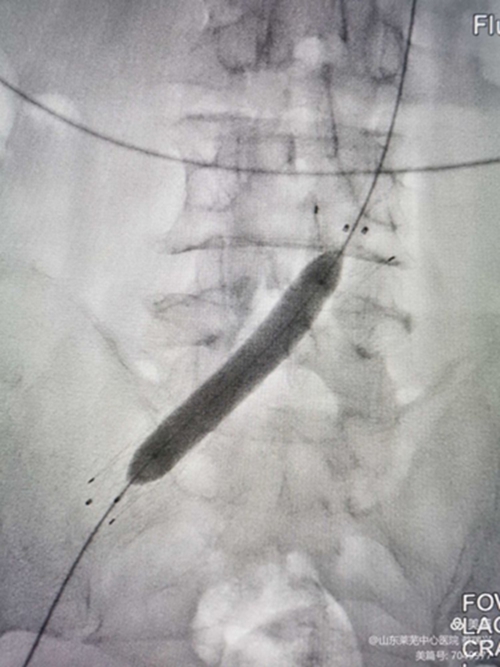

后擴(kuò)滿意后

再造影見狹窄消失,血流順暢。